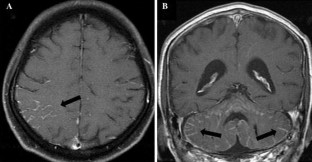

Leptomeningeal carcinomatosis (LMC) is a rare but devastating complication of gastric cancer.

Of the 12 patients, 9 (75%) were male, and the median age was 63 years. Histopathologically, the majority of the patients (83%) had diffuse-type adenocarcinoma. At the time of diagnosis of the LMC, the other major sites of metastasis were the peritoneum (75%) and lymph nodes (50%). The median duration from the diagnosis of gastric cancer to the diagnosis of LMC was 15.6 months. While the treatment strategy changed with time, intrathecal chemotherapy (n = 10), followed by whole brain irradiation (n = 7) and subsequent ventriculo-peritoneal shunt (n = 3) was performed in 10 of the patients. Improvement of neurological functions was observed in 6 of the 10 patients. The median overall survival time from the diagnosis of LMC in all the 12 patients was 60 days. One patient survived for a considerably long period of 532 days.